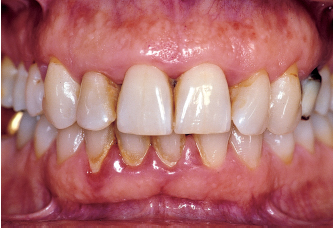

Fig 1-3a In this 40-year-old patient, periodontitis is moderate.

Fig 1-3b Destruction and attachment losses are evenly distributed throughout the dentition and are less than 30%.